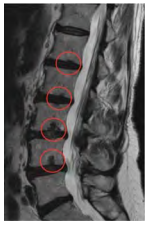

Uma paciente de 62 anos de idade apresenta dor lombar crônica recorrente, com visitas ao PS ortopédico cerca de uma vez por semana. Refere dor difusa em toda a coluna lombar. Ao exame físico, notam-se pontos miofasciais em musculatura lombar bilateral. Os testes neurodinâmicos são negativos. Por insistência da paciente, foi realizado o exame de imagem apresentado.

A respeito desse caso clínico, assinale a alternativa que apresenta a melhor conduta a ser seguida.